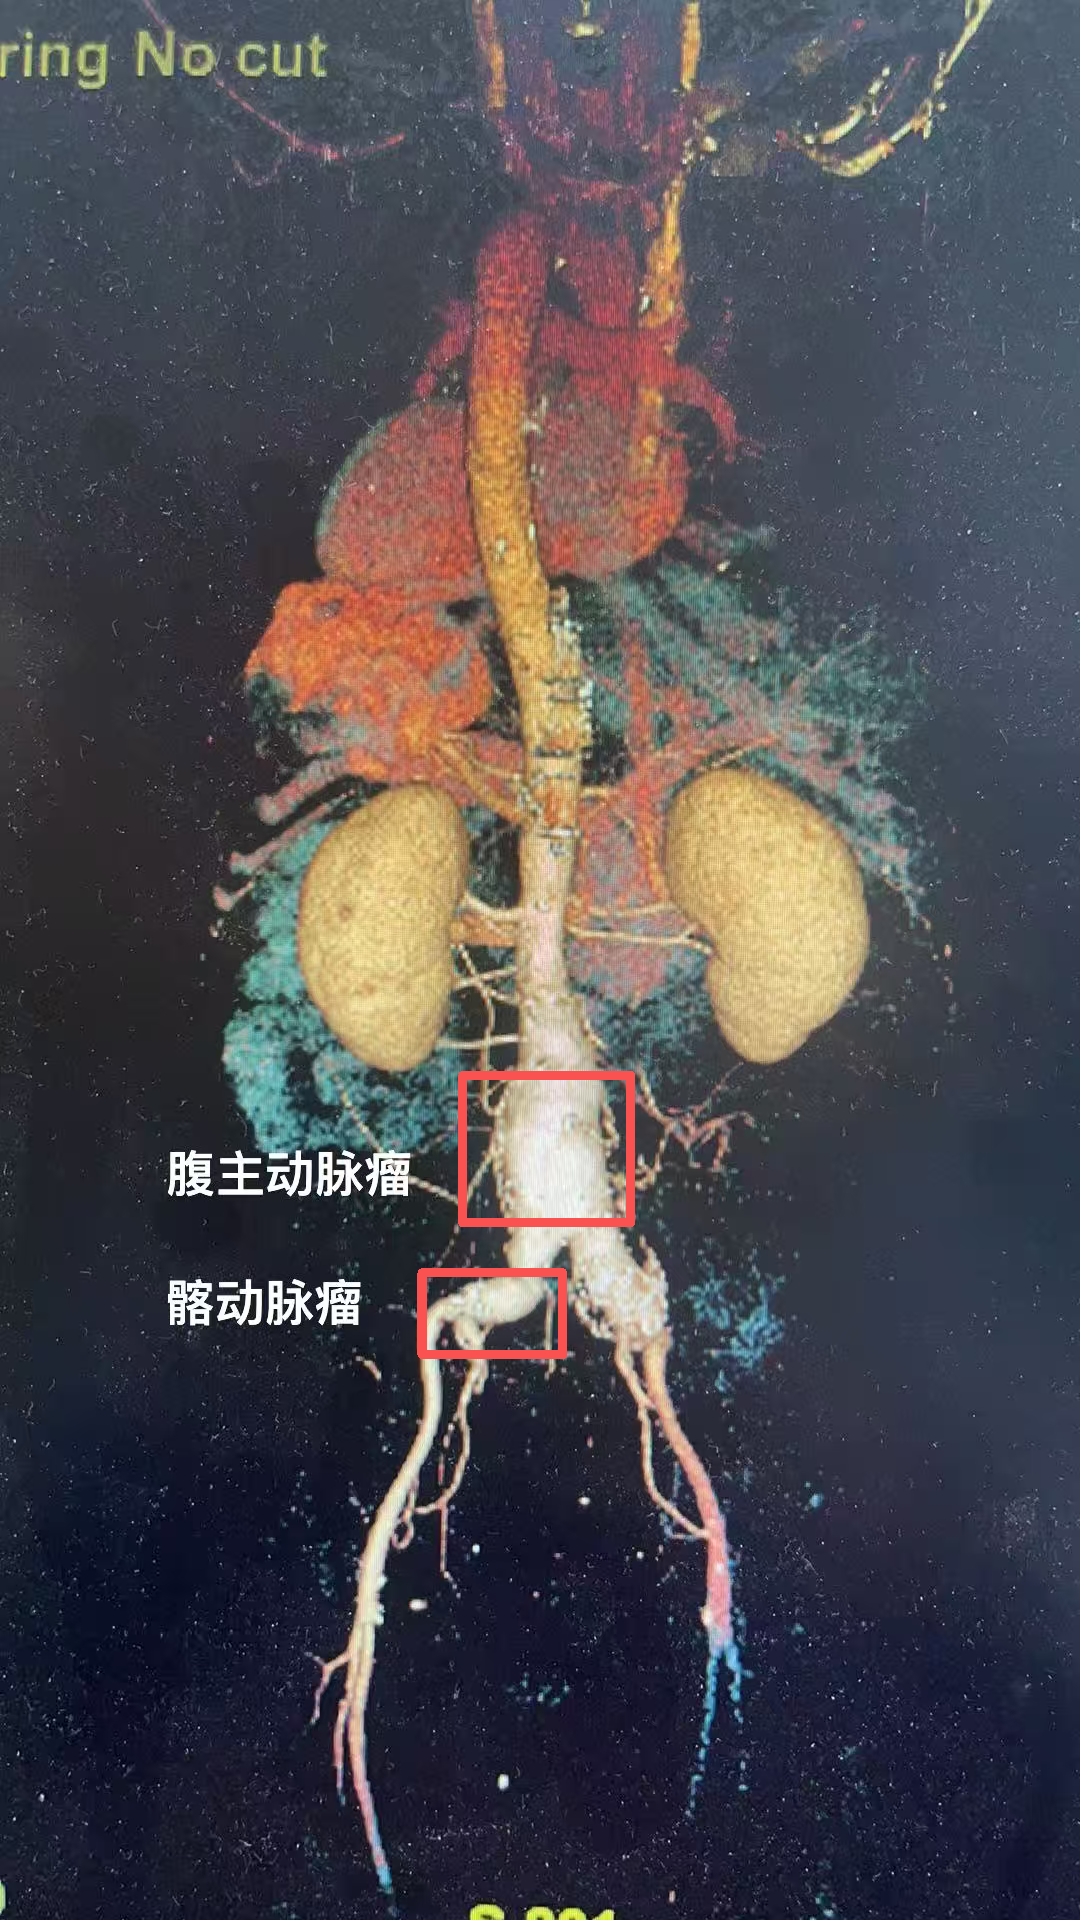

半岛网3月27日讯 (记者 孙贴静)一次再普通不过的体检,两位50岁左右的患者都查出体内藏着随时会引爆的不定时炸弹——腹主动脉瘤合并髂动脉瘤。这些炸弹位置很刁钻,如果按老方法手术,很可能伤及盆腔器官的供血……北京大学人民医院青岛医院血管外科团队在北京大学人民医院血管外科专家、青岛医院血管外科学科主任李清乐教授,青岛医院血管外科执行主任孙念峰、主任医师孙春亮等,成功为两名患者实施了血管外科微创手术(IBE),不仅精准拆弹,还巧妙保住了关键的髂内动脉,目前患者恢复良好,已顺利出院!

这两位患者情况差不多,他们平日里身体并无明显不适,在一次常规体检中,腹部超声检查结果显示,腹主动脉存在瘤样扩张,进一步检查确诊为腹主动脉瘤,并同时累及双侧髂总动脉,形成髂动脉瘤。

瘤子长在什么位置?腹主动脉是人体腹部最粗大的一根动脉,大致位于肚脐的后面、脊柱的前面,负责将心脏泵出的血液输送到下半身。到了肚脐下方约三四指的位置,它分叉成左右两条髂总动脉,继续向双腿延伸。患者情况比较特殊,动脉瘤不仅累及了腹主动脉主干,还向下延伸到了分叉区域。

保住动脉,就是保住功能。这颗炸弹,需要尽快拆除。但手术的最大难点,不仅在于如何封堵动脉瘤,更在于如何保住一条重要的血管髂内动脉。

北京大学人民医院青岛医院血管外科团队用一个通俗的比喻解释了其中关键:腹主动脉分叉后形成的左右两条髂总动脉,每条又分出一条髂内动脉。这条髂内动脉虽然不算粗,却承担着为臀部肌肉、盆腔器官以及会阴部供血的重任。如果为了拆除动脉瘤,简单地把髂内动脉一起封堵掉,患者术后就可能面临一系列棘手的并发症:臀部肌肉间歇性跛行,走几步路就腿酸乏力;盆腔器官缺血,可能影响肠道和膀胱功能;对于男性患者而言,还会增加性功能障碍的风险。因此,手术的目标很明确,既要拆除动脉瘤,又要保住髂内动脉,最大程度地维护他未来的生活质量。